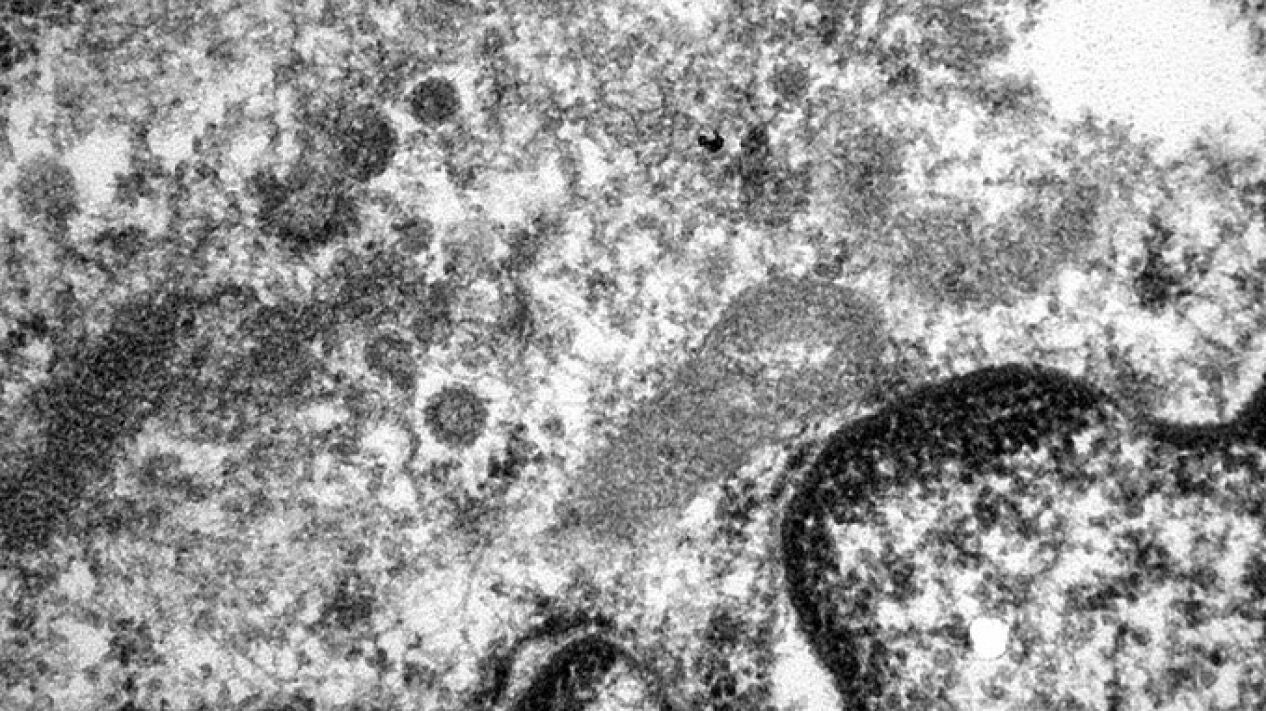

La fotografía que muestra cómo es el coronavirus en los vasos sanguíneos de un paciente infectado

"La imagen del coronavirus más buscada", así publica el Hospital de Barcelona la siguiente micrografía en la que se puede ver al virus dentro de los vasos sanguíneos.

El Hospital del Mar de Barcelona ha compartido y una fotografía tomada con microscopio que muestra cómo es el SARS-CoV-2, el coronavirus causante del COVID-19, dentro de los vasos sanguíneos de un paciente infectado.

En la imagen, tomada por el doctor Josep Lloreta del servicio de Patología de dicho hospital, se puede apreciar la forma redondeada del coronavirus y la corona que le da nombre y que le permite penetrar en las células.

En el tuit donde se puede ver esta imagen, el centro explica que está ampliada por 34.000 con respecto al original. Además, se especifica que la micrografía corresponde a una zona ulcerada en el intestino de un paciente infectado y en ella se puede ver de una parte del núcleo y el citoplasma.